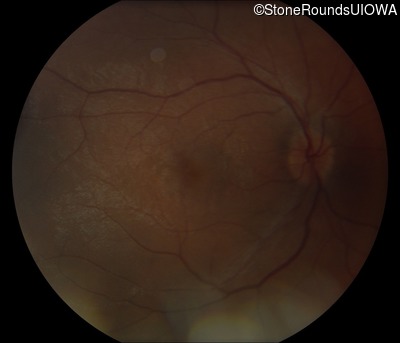

Fundus Photography - Right - 20/30 -2

Exemplar